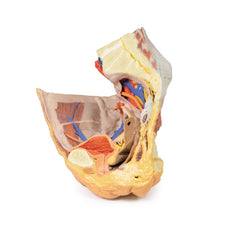

This 3D model represents one of the largest and most complex in the series, consisting of a partial torso from the diaphragm to the proximal thigh with a complete abdominal cavity preserving varying levels of dissection. This 3D model also records the rare, simultaneous occurrence of indirect and direct inguinal hernias allowing for a consideration of the anatomical underpinnings for both conditions. Given the scale of the dissection this 3D model description is divided into discrete parts based on views and regions.

The diaphragm

On the superior aspect of the model the diaphragm is preserved, and while slightly distorted due

to removal of the thoracic ribs through dissection, both domes and costodiaphragmatic recesses can be

appreciated. The fibrous pericardium is present on the superior surface of the central tendon, with the terminal

part of the inferior vena cava visible in the caval foramen. Just lateral to caval foramen is the oesophagus

within the oesophageal hiatus, and then the descending thoracic aorta approaching the aortic hiatus just ventral

to the thoracic vertebrae.

The hypogastrium and iliac regions

In the midline, the bifurcation of the descending abdominal aorta into the

common iliacs (and subsequent division into the internal and external iliacs) can be observed deep to some of

the overlying structures (e.g., testicular vessels, ureters) noted previously. On the right side, the obturator

artery can be seen traversing from its origin towards the anterior aspect of the pelvis. The mirrored merging of

external, internal and common iliac veins into the inferior vena cava is also preserved. Within the confines of

the true pelvis the peritoneum has been retained over the region, covering the urinary bladder adjacent to the

pubic symphysis and obscuring the rectum as it descends from the sigmoid colon. In the right iliac region the

very terminal part of the ileum and caecum with appendix fill the iliac fossa, with the appendix (and

appendicular artery) visible just superficial to the testicular artery, vein and genital branch of the

genitofemoral nerve descending towards the inguinal canal. In the left region, the sigmoid colon descends across

the iliac fossa. As it approaches the anterior abdominal wall, an epiploic appendage contribution to the

indirect hernia can be observed just lateral to the retained inferior epigastric artery.

The inguinal region and perineum

A distinctive and unique feature of this model is the dissection of

simultaneous direct and indirect hernias preserved on the right and left sides, respectively. While most of the

anterior abdominal wall has bee removed, the inferior epigastric arteries (and accompanying veins) have been

retained to allow for interpretation of the herniations. On the right side, a distinct outpouching of the

parietal peritoneum has formed medial relative to the inferior epigastric artery, representing an indirect

herniation event. On the left side, the hernia sac extends laterally relative to the inferior epigastric artery

and into the opened spermatic cord, with continuity of the epiploic appendage from the sigmoid colon into the

sac.

The skin over the perineum has been removed in order to demonstrate both the structure of the penis

(with both the corpus spongiosum and corpora cavernosa contrasted) and the position of the testes and spermatic

cords relative to the anterior abdominal wall. On the right side, which in this individual is impacted by a

direct hernia, the spermatic cord has been left undissected allowing for an appreciation of the external

spermatic fascia from the inguinal region through to the testis. On the left side, the spermatic cord has been

opened and is dominated by the enlarged and varicose testicular vein (reflecting the impact of the indirect

hernia exposed within the cord) just superior to the epididymis and exposed tunica albuginea of the testis.